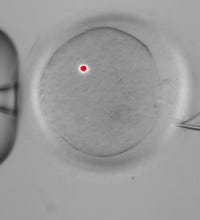

Reproductive technologies that marry DNA from three individuals will receive a trial in the court of public opinion this week. Such technologies may hold promise for averting certain genetically inherited diseases passed down via mutations to mitochondria, the cell’s battery pack. On Feb.25th there will be an advisory committee convening to hear this case.

Reproductive technologies that marry DNA from three individuals will receive a trial in the court of public opinion this week. Such technologies may hold promise for averting certain genetically inherited diseases passed down via mutations to mitochondria, the cell’s battery pack. On Feb.25th there will be an advisory committee convening to hear this case.